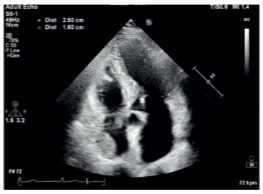

Rhabdomyoma

What is seen in this TTE?

<p>What is seen in this TTE?</p>